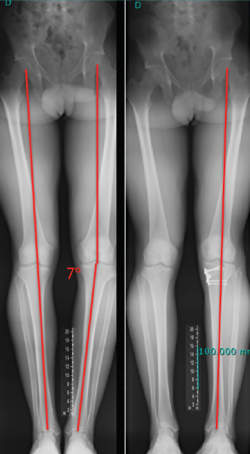

El estudio radiológico recomendado debería incluir proyecciones anteroposteriores y laterales, axiales de rótula, telemétricas de la extremidad inferior y también en posición de Schuss (en carga y con unos 30° de flexión de la rodilla). La radiología simple va a permitir identificar qué técnica quirúrgica se realizó inicialmente y qué material se utilizó para la fijación (Figura 1). La proyección en Schuss permite observar si existen cambios degenerativos en los compartimentos femorotibial interno o externo de la rodilla de forma más precisa que con la radiología simple en decúbito supino. Finalmente, la radiografía telemétrica de las extremidades inferiores va a permitir conocer el eje mecánico de la extremidad. La existencia de deformidades en el plano coronal se ha asociado a un incremento de la solicitación mecánica del LCA y también del riesgo de rotura de la plastia (Figura 2)(21).

Independientemente de las deformidades en el plano axial, las deformidades en el plano coronal, sobre todo el genu varo, se han relacionado también con un incremento de las solicitaciones mecánicas sobre el LCA y secundariamente como factor de riesgo de rotura(45,46).

Figura 2. Paciente de 21 años con antecedente de reconstrucción anatómica del ligamento cruzado anterior (LCA) y ángulo posteroexterno que requirió cirugía correctiva de un genu varo de 7° después de fracasar la reconstrucción ligamentosa.